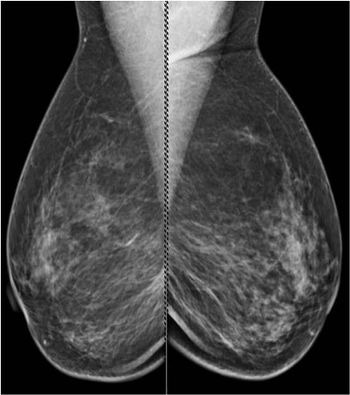

49-year-old patient presented for bilateral screening mammogram as well as bilateral screening ultrasound due to dense breast tissue.